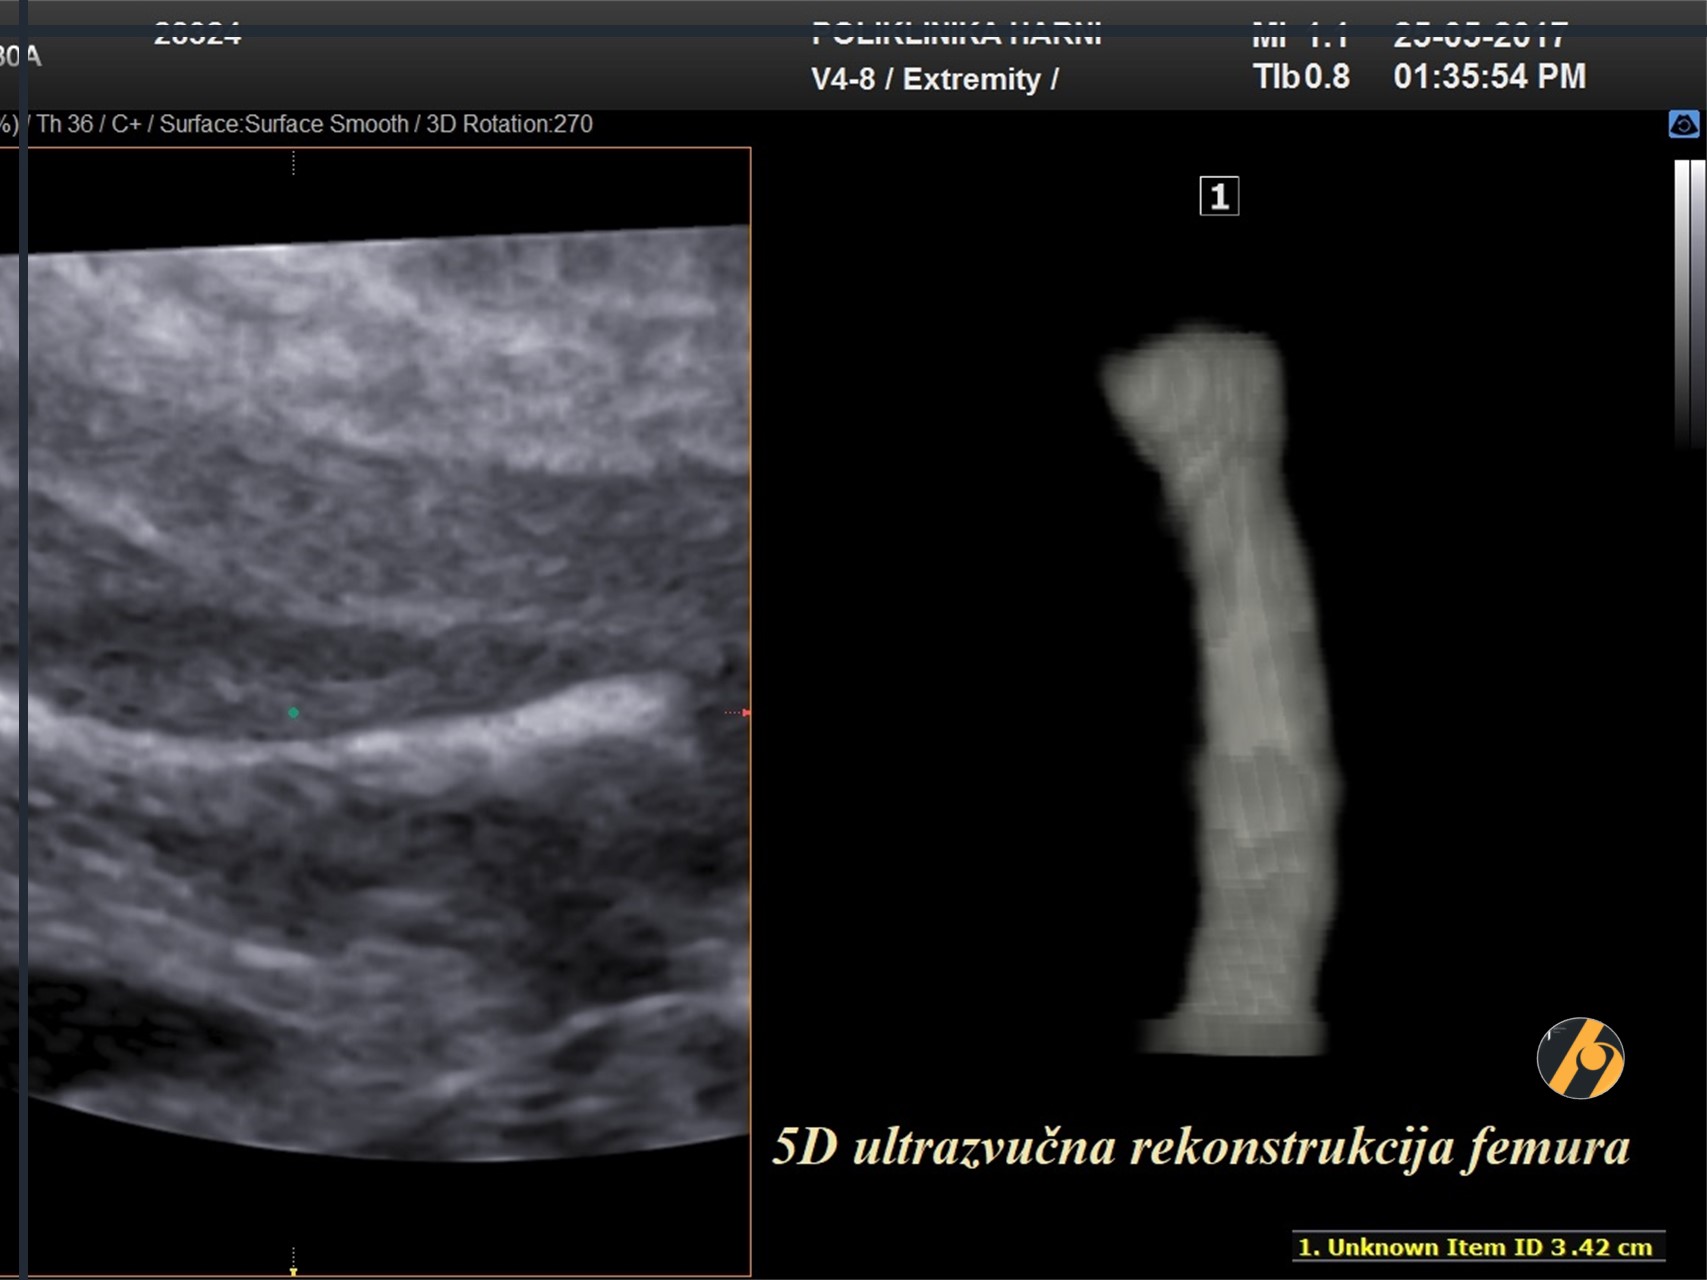

Duljina femura / FL

Optimalan prikaz kosti za mjerenje je kada se jasno prikazuju oba kraja osificiranih metafiza. Mjeri se najdulji prikaz osificirane dijafize.

Ekstremiteti

Obavezan dio anomaly scana je prikazati obje ruke i noge sa svim dugim kostima, angulaciju šakica i stopala u odnosu na podlakticu i potkoljenicu te prikaz prstića ruku i stopala.